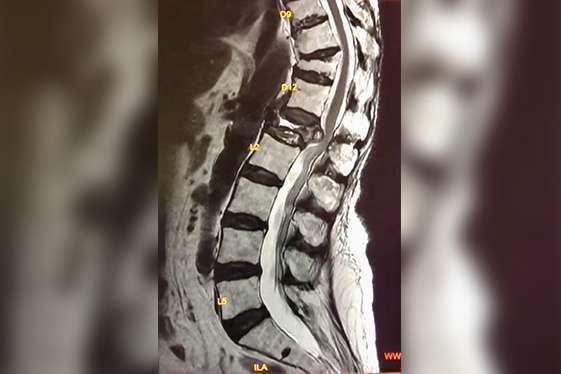

Management of Spine problems

Complete care for a variety of spine problems like cervical spondylosis, lumbar spondylosis, disc prolapse, sciatica, spinal stenosis, fractures, paraplegia, quadriplegia, radiculopathy, tumours, and infections like tuberculosis (TB).